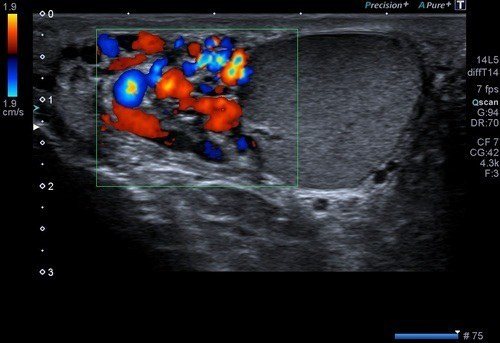

Varikosel testisler komşuluğunda skrotal kese içerisindeki toplardamarlardaki varislerdir. Varikosel olması durumunda skrotal kese içerisindeki ısı artacağı için sperm canlılığı bozulacak ve infertiliteye (kısırlık) sebep olabilecektir. Varikosel tanısı için skrotal renkli doppler ultrason yapılır ve buradaki toplardamar genişlikleri ve yetmezlikleri değerlendirilir. Bu tetkikin sonucunda bir evreleme yapılır. Bu evrelemeye göre hastaya tedavi planlanır.

Ayrıca skrotal renkli doppler ultrason testislerde yerleşimli olası kitlelerin değerlendirilmesine ve skrotal kese içerisindeki epididim adını verdiğimiz organın iltihaplarında tanıda kullanılır.